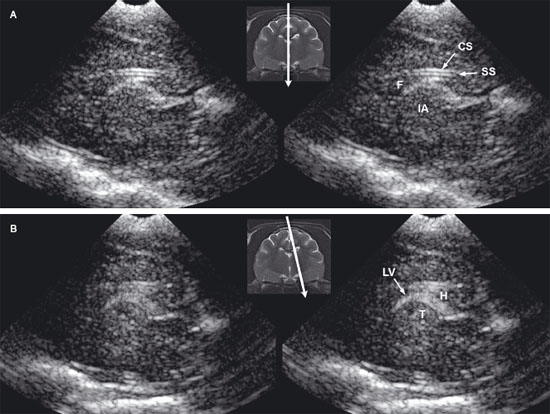

The feline brain can be evaluated by using transverse and longitudinal sonographic planes (Figures 1.5 and 1.6).

Figure 1.6. Sagittal to parasagittal sonograms of the brain of a normal 1-week-old kitten. A: Midline sagittal sonogram. B: Parasagittal sonogram with the beam angled lateral to the midline. CS, callosal sulcus; F, fornix; H, hippocampus; IA, interthalamic adhesion; LV, lateral ventricle; SS, splenial sulcus; and T, thalamus. The arrow in the magnetic resonance image insert shows sagittal and parasagittal planes corresponding to the sonograms.